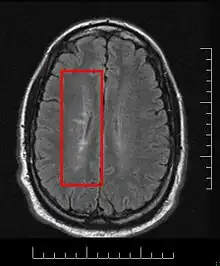

Normally MS lesions are small ovoid lesions, less than 2 cm. long, oriented perpendicular to the long axis of the brain's ventricles [18] Often they are disposed surrounding a vein[19]

Active and pre-active lesions appear as hyperintense areas under T2-weighted MRI. Pre-active lesion here refers to lesions localized in the normal appearing white matter, without apparent loss of myelin but nevertheless showing a variable degree of oedema, small clusters of microglial cells with enhanced major histocompatibility complex class II antigen, CD45 and CD68 antigen expression and a variable number of perivascular lymphocytes around small blood vessels[20]

This morphologic appearance was named Dawson's fingers by Charles Lumsden, after the Scottish pathologist James Walker Dawson,[31] who first defined the condition in 1916.

Dawson's fingers

"Dawson's fingers" is the name for the lesions around the ventricle-based brain veins[32][33] of patients with multiple sclerosis and antiMOG associated encephalomyelitis[34]

Though once thought to be specific of MS, it is known not to be the case.[35]

The condition is thought to be the result of inflammation or mechanical damage by blood pressure[30] around long axis of medular veins.

Dawson's fingers spread along, and from, large periventricular collecting veins, and are attributed to perivenular inflammation.[36]